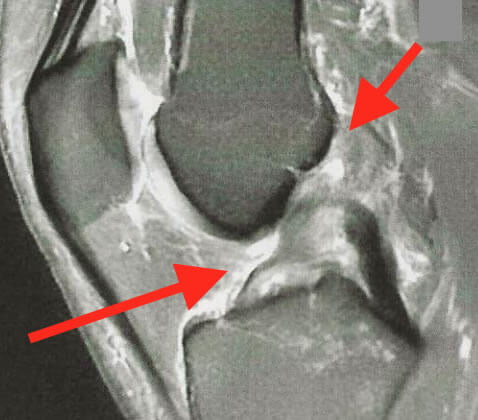

Une IRM est indispensable après une entorse, surtout si l'examen clinique n'est pas concluant.

Elle permet de confirmer la rupture et de préciser les lésions associées, ligamentaires et/ou méniscales, associées.

Les extrémités du ligament croisé antérieur rompu ne restent pas en contact après la rupture, comme le montre les images de l'IRM (à de très rares exceptions près). Le caillot de fibrine ne peut donc pas se former.